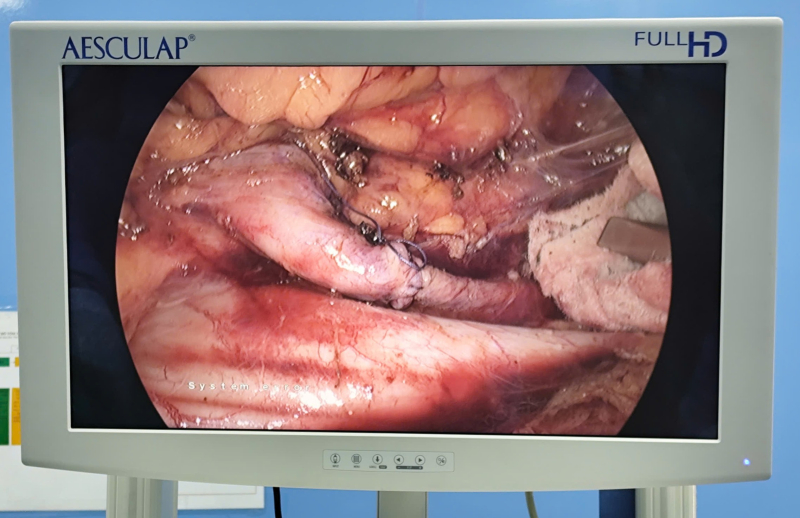

Hình ảnh: Niệu quản phải được phẫu thuật chuyển vị ra trước tĩnh mạch chủ dưới.

Quá trình phẫu thuật được thực hiện tỉ mỉ, khéo léo nhằm bóc tách an toàn hiệu quản, tránh tổn thương tĩnh mạch chủ và các cấu trúc lân cận. Đồng thời tiến

hành tán sỏi niệu quản trái, đặt sonde JJ 2 bên.

Sau gần 2 giờ, Kíp phẫu thuật do BSCKII Dương Xuân Hiệp, Trưởng khoa Ngoại tổng hợp, phụ trách phòng TCCB cùng ê kíp đã phẫu thuật thành công, niệu quản được tái tạo lưu thông tốt, chức năng thận được bảo tồn tối đa. Sau mổ, bệnh nhân hồi phục tốt, tiểu tiện bình thường.